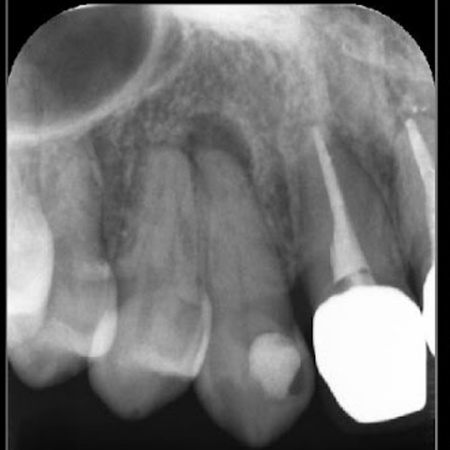

レントゲン検査を行った結果、右上前歯の歯根の先端に膿が溜まる根尖(こんせん)病巣が確認できました。

歯ぐきにできた膨らみはフィステルと呼ばれ、歯や周囲の組織に感染が広がった際に膿を体外に排出するために自然に形成される通り道です。

歯ぐきに白く膨らんだできものとして現れ、見た目はニキビに似ていますが、これは内部に感染が潜んでいるサインとされています。

感染の拡大を防ぎ歯を温存するためには、歯根の内部に入り込んだ細菌を徹底的に除去し清掃・消毒を行う根管治療が必要と診断しました。